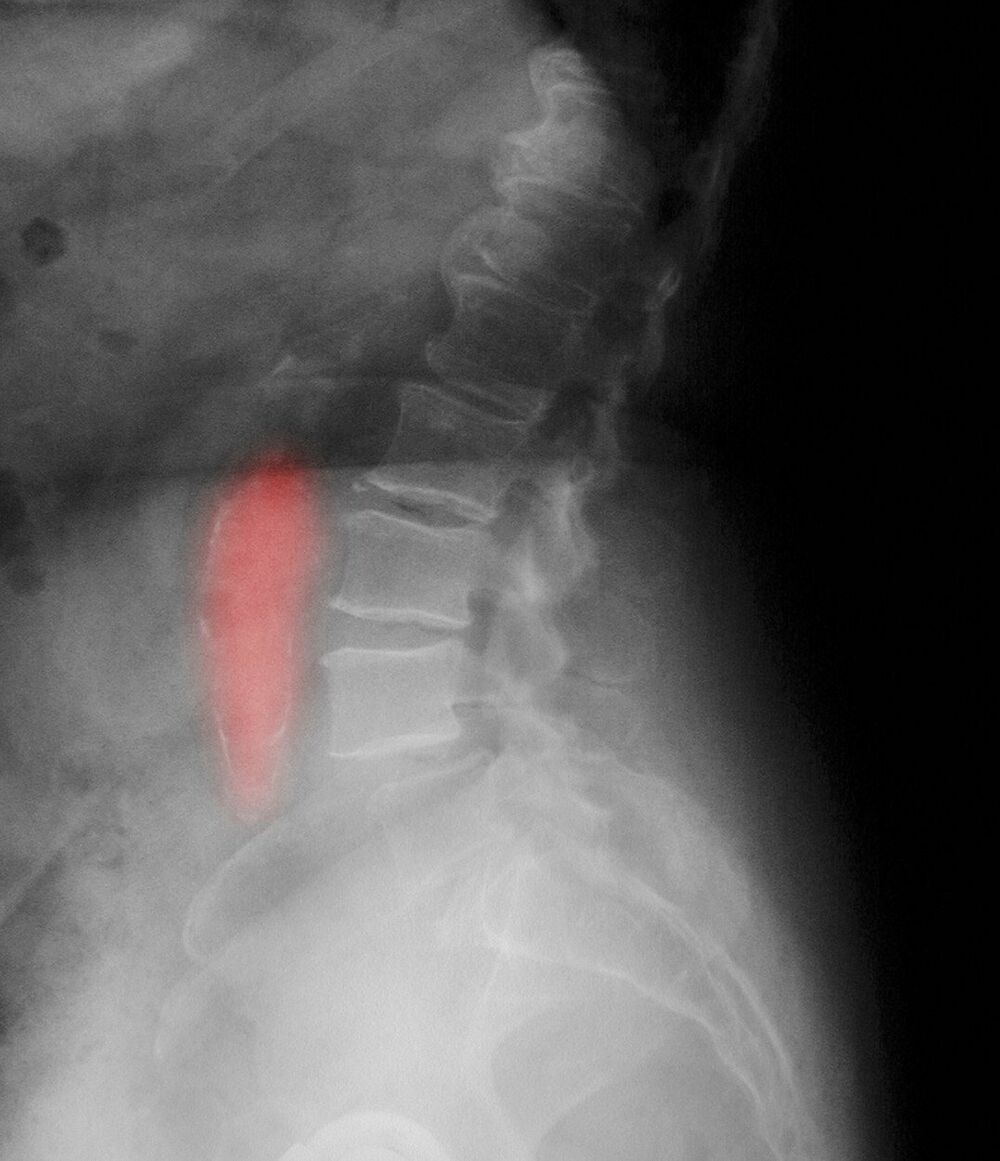

Kada se krvni sud, arterija, uveća više od 50% svoje normalne širine možemo govoriti o aneurizmi. Najčešća njena lokalizacija je u trbušnom delu gde normalno prečnik aorte iznosi od 16-20 mm. Kada prečnik pređe 30 mm možemo govoriti o početnom stadijumu aneurizme abdominalne aorte. Ovo širenje aorte dešava se postepeno i traje godinama.

Posebno zabrinjava porast prečnika od 5 mm godišnje kada se često brzo odlučujemo za operativno lečenje. Pogađa češće muškarce, ali se u poslednje vreme sve češće pronalazi i kod žena. Starosna dob pacijenata je obično u sedmoj deceniji i kasnije, ali se sve češće viđa i kod ljudi u pedesetim godinama.

Kada aneurizma pređe prečnik od 6 cm smatramo da ova veličina predstavlja jedno urgentno stanje koje zahteva brzo lečenje. Najbolje bi bilo da se aneurizma leči kada nema simptoma, planiranom operacijom. Operativno lečenje podrazumeva zamenu obolelog dela aorte sa sintetskim graftom, pletenim crevom od materijala sličnih teflonu koji su otporni na istezanje.

Jedna od karakteristika abdominalne aneurizme jeste da ona svojim pulsacijama znatno oštećuje tela kičmenih pršljenova gde može da dovede do stanja koje imitira bolesti kičme i međupršljenskih diskova. Ovo naglašavam, jer neretko ovi pacijenti gube vreme u dijagnostici i lečenju bolesti kičmenog stuba. Na kraju, preporuka bi bila da svi ljudi stariji od 55 godina idu jednom godišnje na pregled trbuha ultrazvukom da bi se eventualno otkrila aneurizma u svom početnom stadijumu. Takođe bi se kontrolama trebali podvrgnuti ljudi koji imaju bliskog srodnika koji je imao aneurizmu jer pojava porodične sklonosti nije tako retka. Faktore rizika bi trebalo svesti na minimum uz redovno uzimanje adekvatne terapije za hronične bolesti.